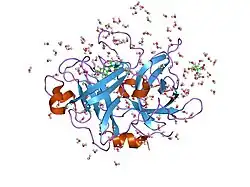

Urokinase is a 411-residue protein, consisting of three domains: the serine protease domain (consisting of residues 159–411), the kringle domain (consisting of residues 50-131), and the EGF-like domain (consisting of residues 1-49). The kringle domain and the serine protease domain are connected by an interdomain linker or connecting peptide (consisting of residues 132–158). Urokinase is synthesized as a zymogen form (prourokinase or single-chain urokinase), and is activated by proteolytic cleavage between Lys158 and Ile159. The two resulting chains are kept together by a disulfide bond between Cys148 and Cys279.[9]

The most important inhibitors of urokinase are the serpins plasminogen activator inhibitor-1 (PAI-1) and plasminogen activator inhibitor-2 (PAI-2), which inhibit the protease activity irreversibly. In the extracellular matrix, urokinase is tethered to the cell membrane by its interaction to the urokinase receptor.